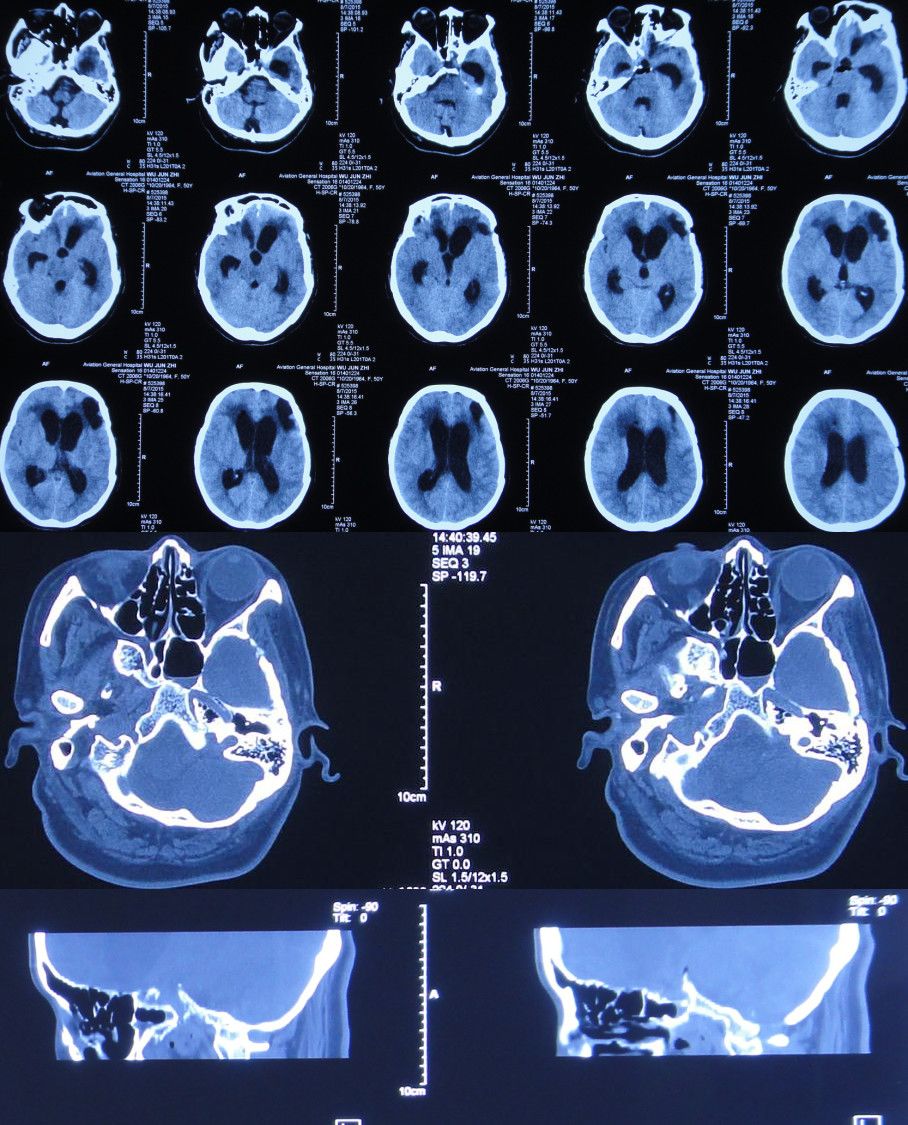

入院后第1天即2015年8月8日,复查头CT头:脑脊液蝶窦瘘征象。脑室扩张,双侧额叶片状密度减低,左侧额叶软化灶形成;脑沟、裂变浅;鞍上池及右侧脑室前角积气(图17)。

图17:2015年8月8日头CT:脑室扩张,鞍上池及右脑室前角积气